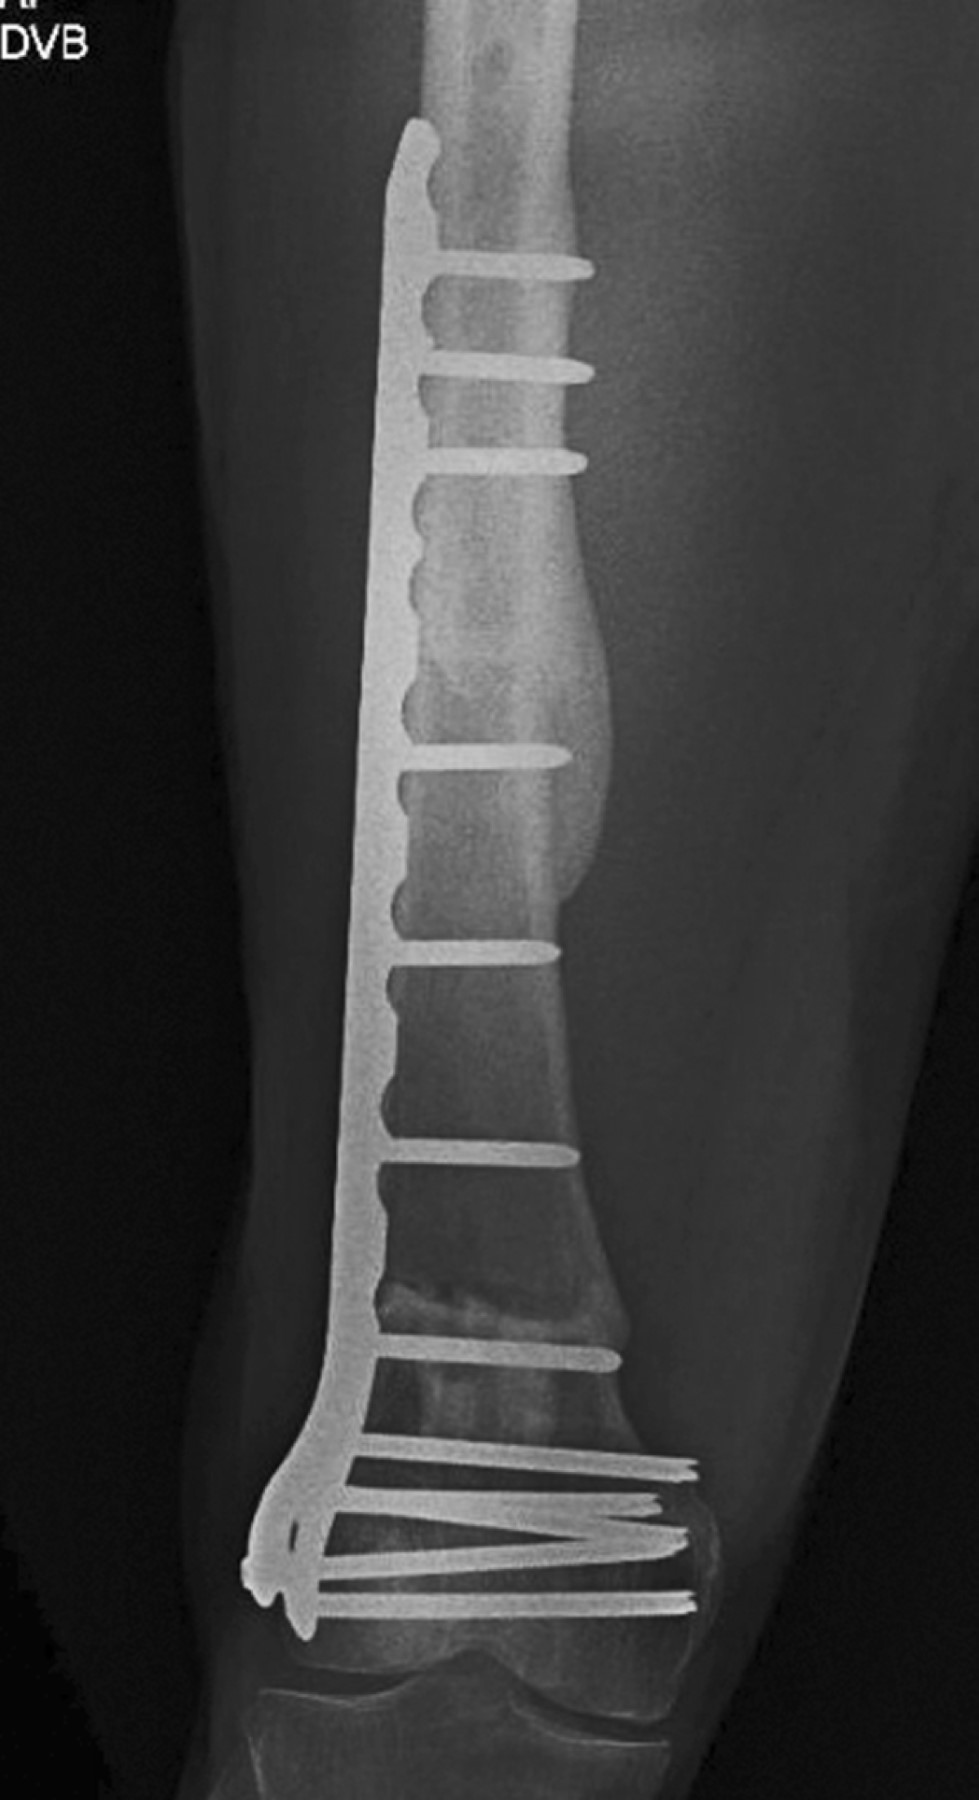

Femoral bone reconstruction after tumor resection, a case report and literature review

Chondrosarcoma are malignant tumors constituted by cartilaginous tissues, the second most common type after osteosarcoma among musculoskeletal tumors, as a general rule they are not sensitive to chemotherapy nor radiotherapy, therefore the treatment involves wide surgical resection with limb salvage, resulting in a bone defect that needs to be reconstructed. reconstruction options available range from endoprostheses, adjuvants after curettage or biological reconstruction using autograft or allograft. Here is a clinical case report of a male patient with massive femoral bone loss, following the resection of a central chondrosarcoma; the bone reconstruction was performed using segmental bone allograft and autograft in combination with platelet rich plasma (PRP), bone marrow aspirate (BMA) and Gelfoam, the reconstruction was stabilized with osteosynthesis material, specifically a locked compression plate (LCP). Strict follow-up was conducted until graft consolidation and integration, which occurred 12 months after the latest surgery. This technique is based on adherence to the principles of the recently introduced "diamond concept", which provides guidelines for the best possible intervention thus increasing the success rate of reconstruction and consolidation. With these strategies, a definitive treatment for bone loss is offered, which is technically accessible for orthopaedic surgeons, reproductible and cost-effective for the patient.

Figure 3